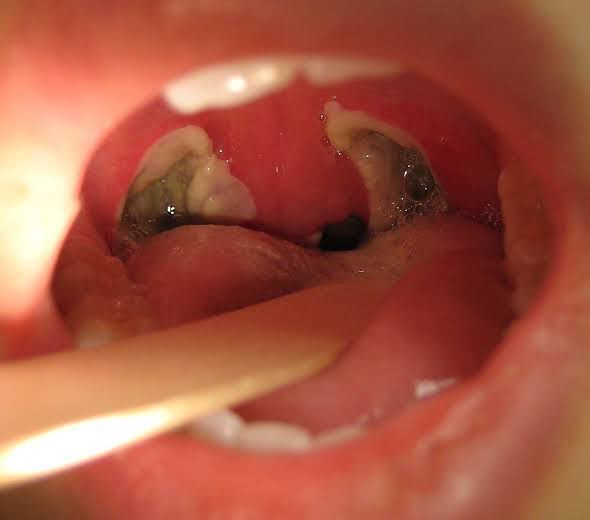

Tonsillectomy Complications Tonsillectomy is a simple surgical procedure where tonsils are removed. Following complications can arise: 1. Haemorrhage: Bleeding after operation. It is classified into 3 types: Primary haemorrhage: Haemorrhage during operation Reactionary haemorrhage: Within 24 hours in recovery. Common causes are ligature slippage, rise in BP and violent efforts Secondary haemorrhage: Commonly seen on 5th post-operative day. Usually a result of bacterial infection. 2. Injury to the cavity 3. Blood aspiration 4. Anaesthetic complications 5. Injury to palate 6. Referred earache 7. Tonsillar remnants